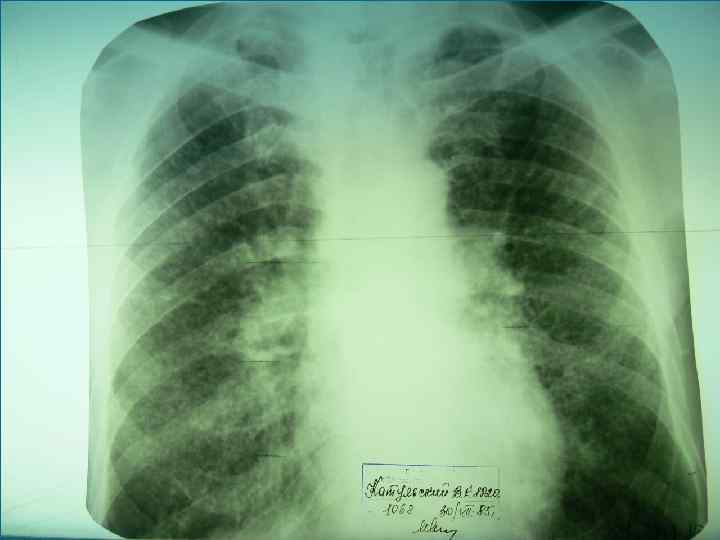

Рентгенологическая картина Спустя 10 -14 дней болезни появляются множественные мелкие / до 2 мм/ однотипные очаги на всем протяжении легких, создается впечатление о более массивной диссеминации в средних отделах. Очаги округлой формы, малой интенсивности, контуры нечеткие, часто расположены в виде цепочки вдоль сосудов. Сосудистый рисунок обеднен